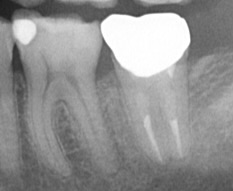

左下1番奥の歯肉が腫れて痛みが出て他院へ受診。抜歯と言われ当院へ保存できないかとのことで来院。マイクロエンド(精密根管治療)にて治癒し保存できた症例。

| 治療内容 | マイクロエンド、セラミッククラウン |